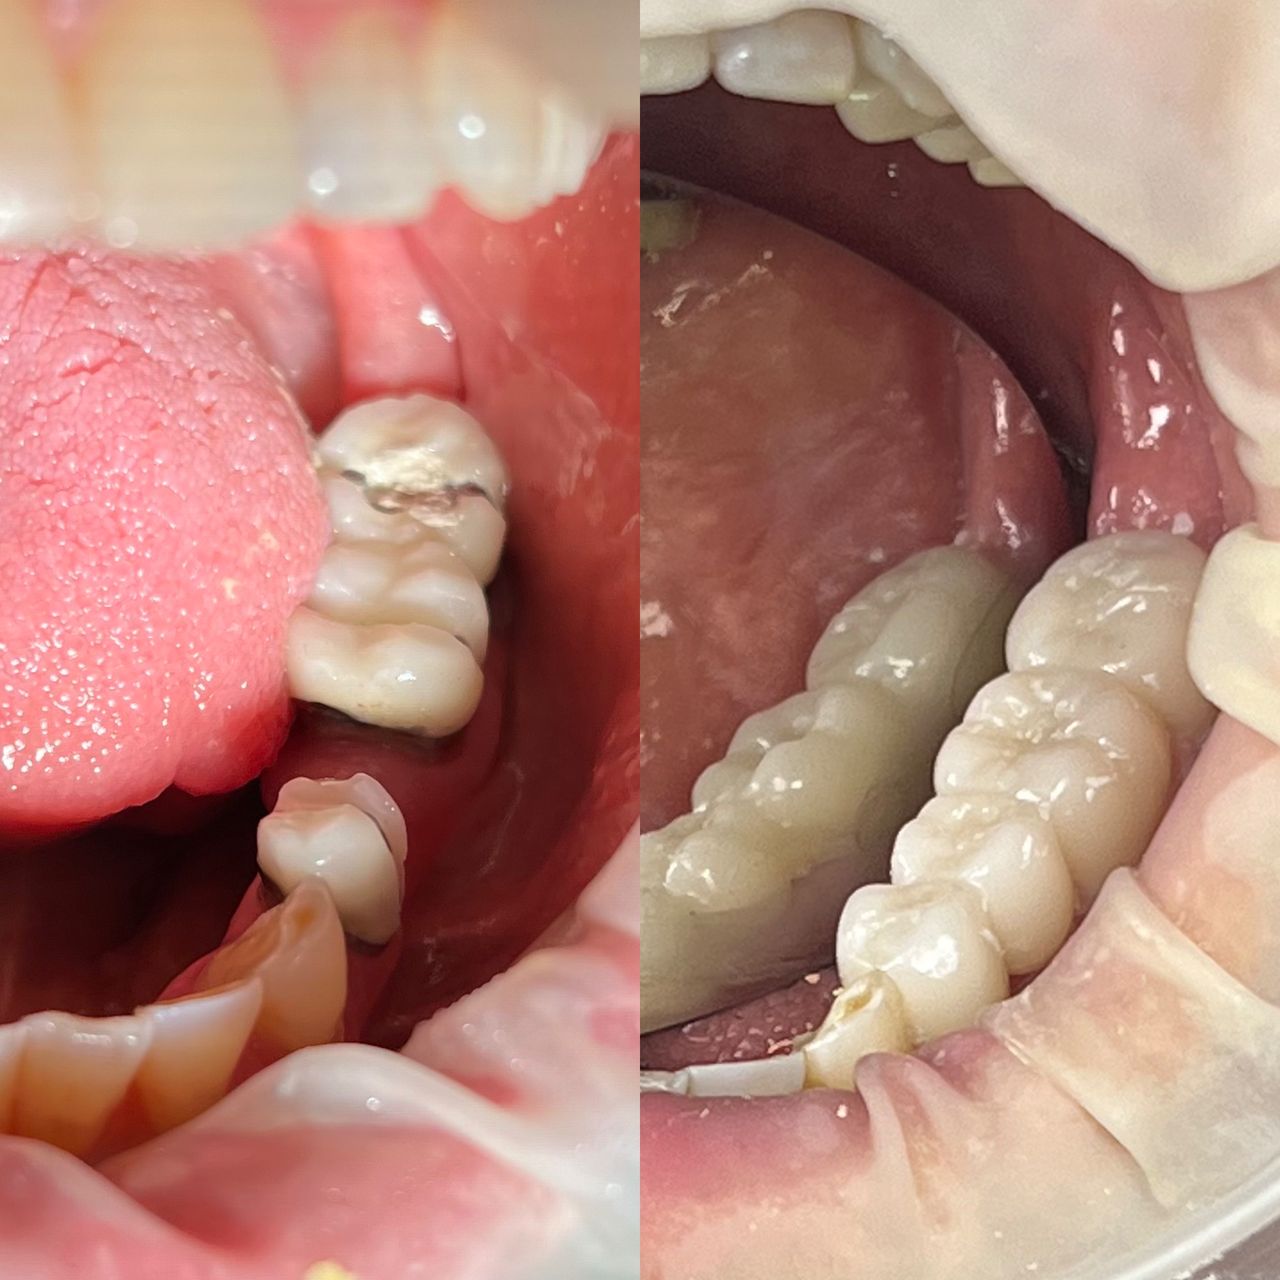

- Odontología estética

- Rehabilitación bucal

- Implantología dental